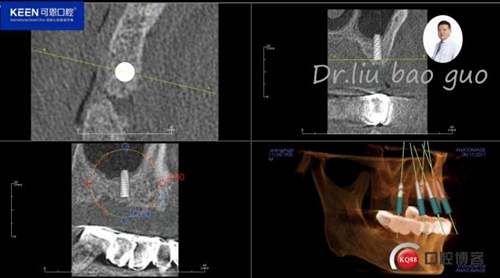

手術(shù)前種植軟件設(shè)計(jì)方案

數(shù)字化種植導(dǎo)板設(shè)計(jì)及制作

檢 查:顏面對(duì)稱,無(wú)腫脹、畸形、腫物及竇道;顳下頜關(guān)節(jié)左右對(duì)稱,頦點(diǎn)居中,面下1/3協(xié)調(diào)。開口度正常無(wú)偏斜,雙側(cè)關(guān)節(jié)動(dòng)度一致,關(guān)節(jié)無(wú)彈響無(wú)雜音;咀嚼肌無(wú)壓痛;17-27缺失,牙齦無(wú)明顯異常,CT示:牙槽骨寬度,高度尚可。